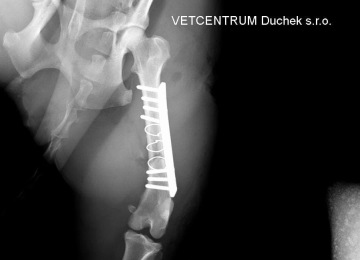

Maxíkova operace byla provedena v inhalační anestézii Isofluranem, před operací dostal Maxík nitrožilně antibiotika. Tříštivá zlomenina stehenní kosti, kde byly 4 fragmenty (úlomky), byla řešena nejprve fixací největšího fragmentu ke kosti dvěma cerklážemi a pak přemosťující ploténkou se sedmi šrouby. Cílem bylo zachovat osu končetiny, funkčnost kyčelního a kolenního kloubu a přiblížit úlomky co nejvíce ke kosti. Jak je vidět na pooperačním RTG snímku, krásně se to podařilo. Max bude brát ještě týden ATB, léky na bolest dle potřeby a modřina vzniklá během úrazu se mu bude mazat Heparoidem. Další RTG jsou plánovány 3-4 týdny po operaci. Zlomenina srůstá po operaci obvykle 6-8 týdnů.